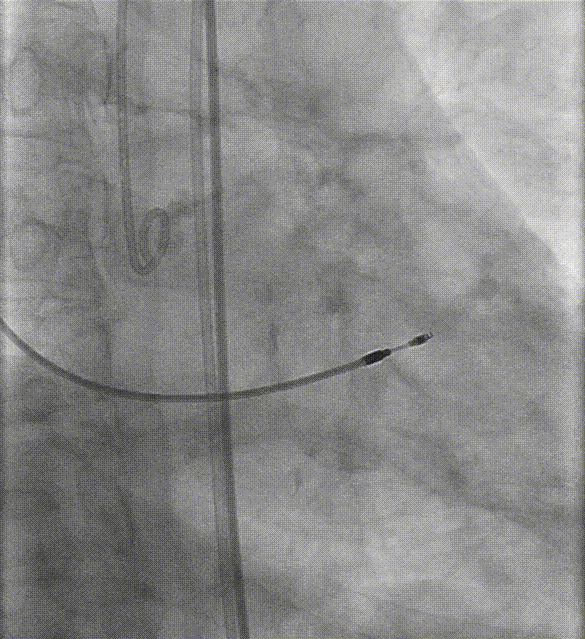

边打造影剂边缓慢撤20F沛嘉大鞘,发现血管夹层

沿导丝送入10mm×100mm覆膜支架至左髂动脉-股总动脉

复查下肢造影显示右髂总动脉-右股总动脉明显狭窄

更换V18导丝后再次送入6.5×60mm赛禾外周冲击波球囊,充盈至4atm下进行一个周期的脉冲治疗

复查右侧髂总动脉-股总动脉造影较前狭窄明显减轻

选择J头导丝带JR4.0造影管翻山选择性造影左侧髂总动脉-股总动脉未见明显狭窄及夹层